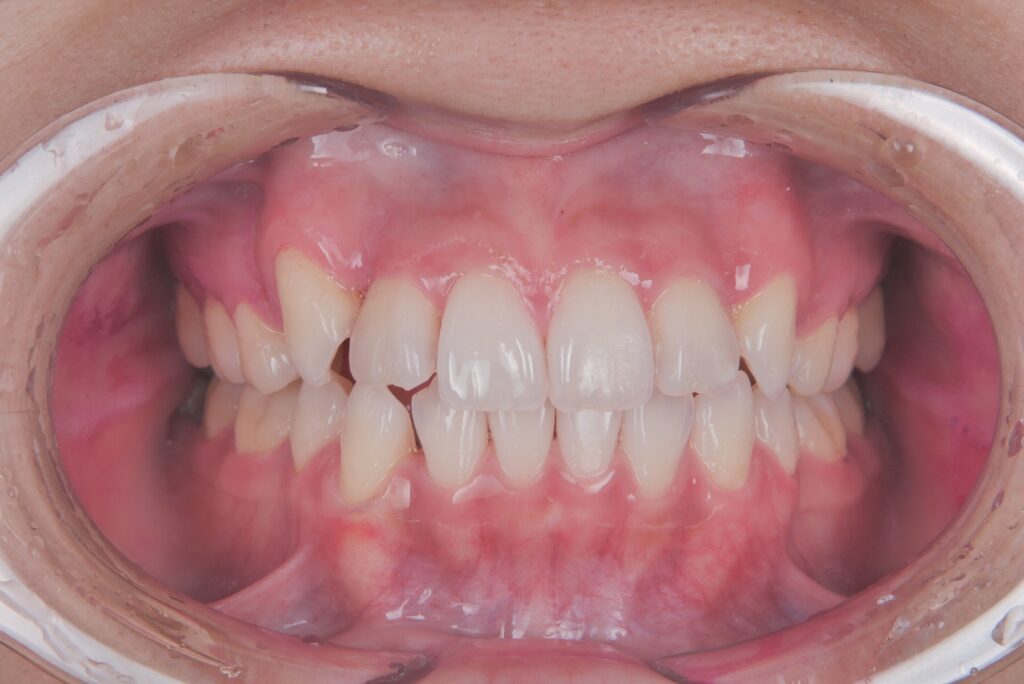

例えばこのケースは1年後の結婚式までにある程度歯並びをきれいにしたいとおっしゃって来られた患者様です。

矯正開始時

治療開始10ヶ月後

右上の八重歯はだいぶ改善して来たのですが、移動量が大きかったため、装置と歯との間に空隙を認めております。

これくらい浮きがある状態だと資料を撮り直して、新しい装置を作ることもありますが、それだと時間のロスになりますし、また結婚式には間に合いません。

そこで結婚式に少しでもいい状態で迎えていただくために、リカバリーでゴムかけを行いました。

下記が2ヶ月後の写真です。

治療開始1年後(治療途中です)

八重歯の部分がしっかり改善していることがわかります。

豊富な経験を積むことで、ズレがでてきた場合にすぐに新しい装置を作り直したほうがいいのか、それとも何かリカバリーをしたほうがいいのかを的確に判断することが無駄のない進行には、とても大切です。

この方は、この状態で結婚式を迎えることができましたので、とても喜んでいただきました。